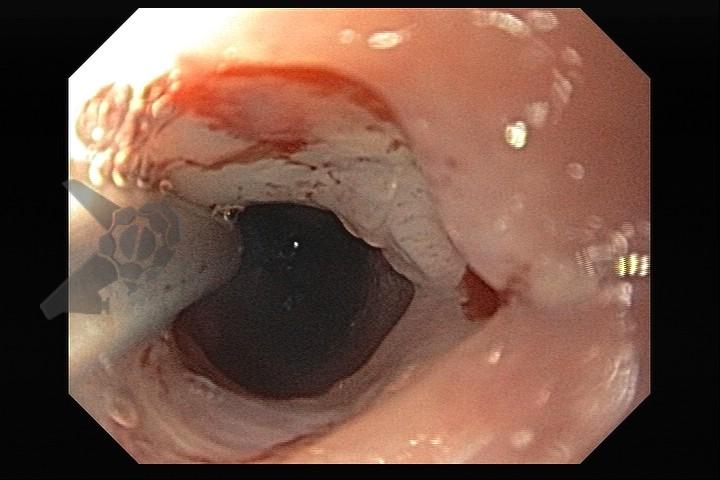

Esôfago de Barrett e Vigilância Endoscópica: o que as diretrizes recomendam e o que o BOSS Trial revela

O esôfago de Barrett constitui a principal lesão precursora desse tipo de neoplasia, razão pela qual múltiplas sociedades médicas recomendam a vigilância endoscópica periódica como estratégia para detecção precoce de displasia e câncer inicial. Entretanto, as evidências que embasam a vigilância endoscópica em pacientes com esôfago de Barrett, em especial no que se refere ao intervalo ideal entre os exames, permanecem limitadas já que a maioria vem de estudos observacionais. Estudos populacionais indicam risco anual relativamente baixo de progressão para adenocarcinoma, variando de 0,12% a 0,22%¹. Portanto, atualmente, a qualidade da evidência que sustenta a vigilância endoscópica é muito baixa.

As recomendações de vigilância endoscópica para pacientes com esôfago de Barrett apresentam pequenas variações entre as sociedades americana e europeia. A diretriz da American College of Gastroenterology (ACG) orienta que, na ausência de displasia, pacientes com segmentos <3 cm sejam submetidos à vigilância a cada 5 anos, enquanto aqueles com segmentos ≥3 cm devem ser acompanhados a cada 3 anos. Para casos de displasia de baixo grau não tratados endoscopicamente, a recomendação é de vigilância semestral no primeiro ano, seguida de acompanhamento anual².

Já a European Society of Gastrointestinal Endoscopy (ESGE) estabelece intervalos de 5 anos para segmentos de 1 a 3 cm e de 3 anos para segmentos entre 3 e 10 cm, recomendando ainda que pacientes com segmentos ≥10 cm sejam encaminhados a centros especializados³.